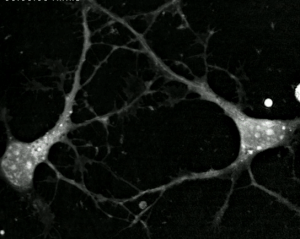

Cosa hanno a che vedere questi eventi? Tantissimo. Il batterio inglobato dalla cellula un miliardo e mezzo di anni fa si è evoluto in un mitocondrio. Le cellule del corpo umano, con alcune eccezioni, contengono ora tanti mitocondri (i batteri si replicano) che continuano a vivere in simbiosi con le nostre cellule, cioè con noi. Tra le altre cose, i mitocondri sintetizzano specifiche molecole che poi sono utilizzate come fonti di energia. Metaforicamente, quindi, i mitocondri sono il personale delle centrali energetiche delle nostre cellule.

In tutto il mondo, migliaia di scienziati e scienziate conducono ricerche sui mitocondri per capire meglio come funzionano, allo scopo di aiutare a curare le malattie mitocondriali. Sapendo che i mitocondri erano batteri, non sorprende che abbiano il loro DNA. È affascinante che nelle nostre cellule non c'è solo il nostro DNA, nel nucleo della cellula, ma anche quello di centinaia o migliaia – per alcune cellule milioni – di mitocondri nostri simbionti. Il DNA dei mitocondri può acquisire mutazioni, che possono causare malattie. Affascinante anche che ereditiamo i mitocondri solo dalle nostre madri: tutti i mitocondri che avremo discendono da quelli dall'ovulo che ci ha originato.